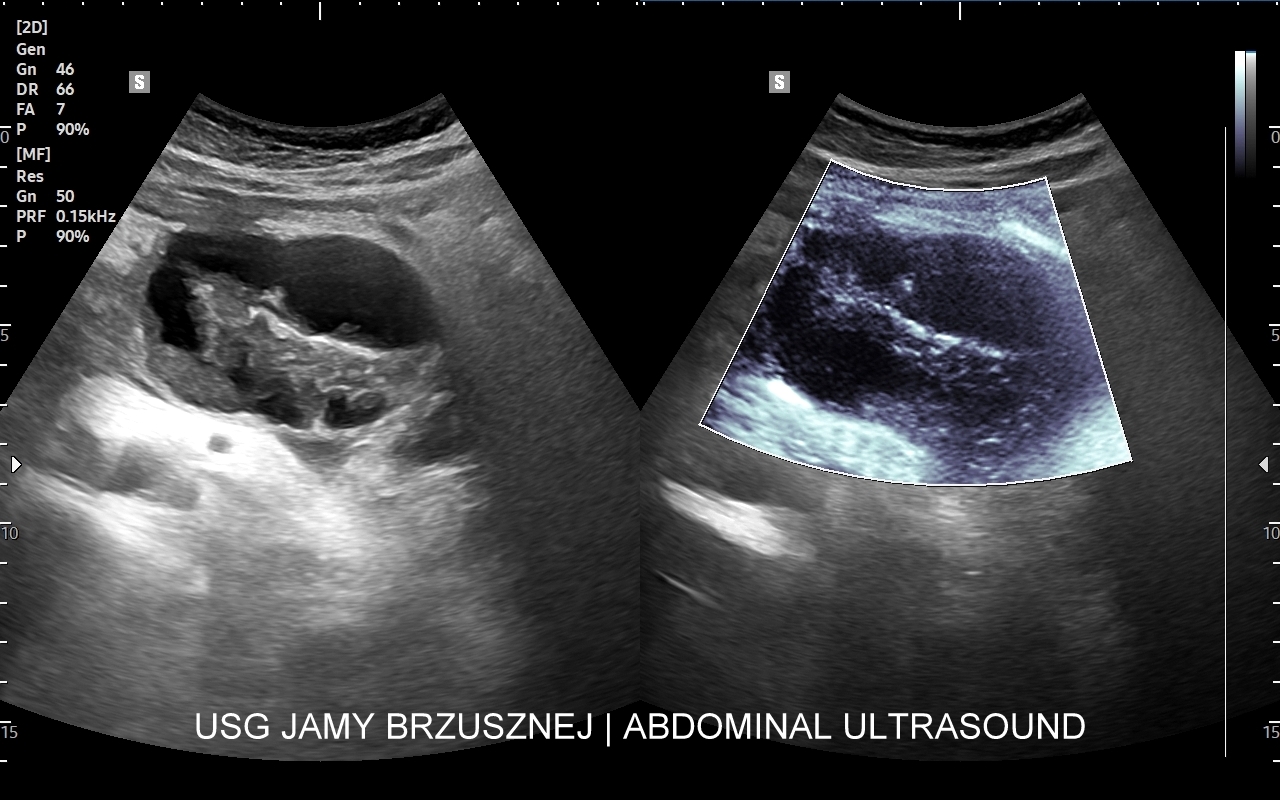

Badanie multiparametryczne MPUS jamy brzusznej

Rozwinięciem standardowego badania USG jamy brzusznej jest badanie multiparametryczne MPUS (ang. multiparametric ultrasound), w ramach którego wykorzystuje się różnorodne, nowoczesne modalności sonograficzne, takie jak tryby mikrounaczynienia MVI, B-flow, elastografię, ilościową ocenę stłuszczenia wątroby QUS, czy tryb Dopplera spektralnego, a to wszystko w celu uzyskania dodatkowej oceny funkcjonalnej i biologicznej struktur, narządów oraz tkanek jamy brzusznej. Obrazowanie MPUS niejednokrotnie poprawia także wizualną ocenę narządów wewnętrznych, czego przykładem jest zastosowanie trybu MVI w ramach bezkontrastowej angiografii sonograficznej naczyń oraz w ocenie guzów nerek. Klasycznymi i najczęstszymi zastosowaniami badania MPUS są jednakże funkcjonalna ocena wątroby w kierunku stłuszczenia, zwłóknienia, zapalenia i nadciśnienia wrotnego, a także ocena żywotności i funkcji nerek.

• Możliwość rozszerzenia zakresu badania USG w razie wystąpienia konieczności. Praktycznymi przykładami są zastosowanie trybu MVI w przypadku wykrycia guzka w nerce, czy przeprowadzenie badania elastograficznego i dopplerowskiego w wypadku stwierdzenia nieprawidłowego obrazu wątroby.